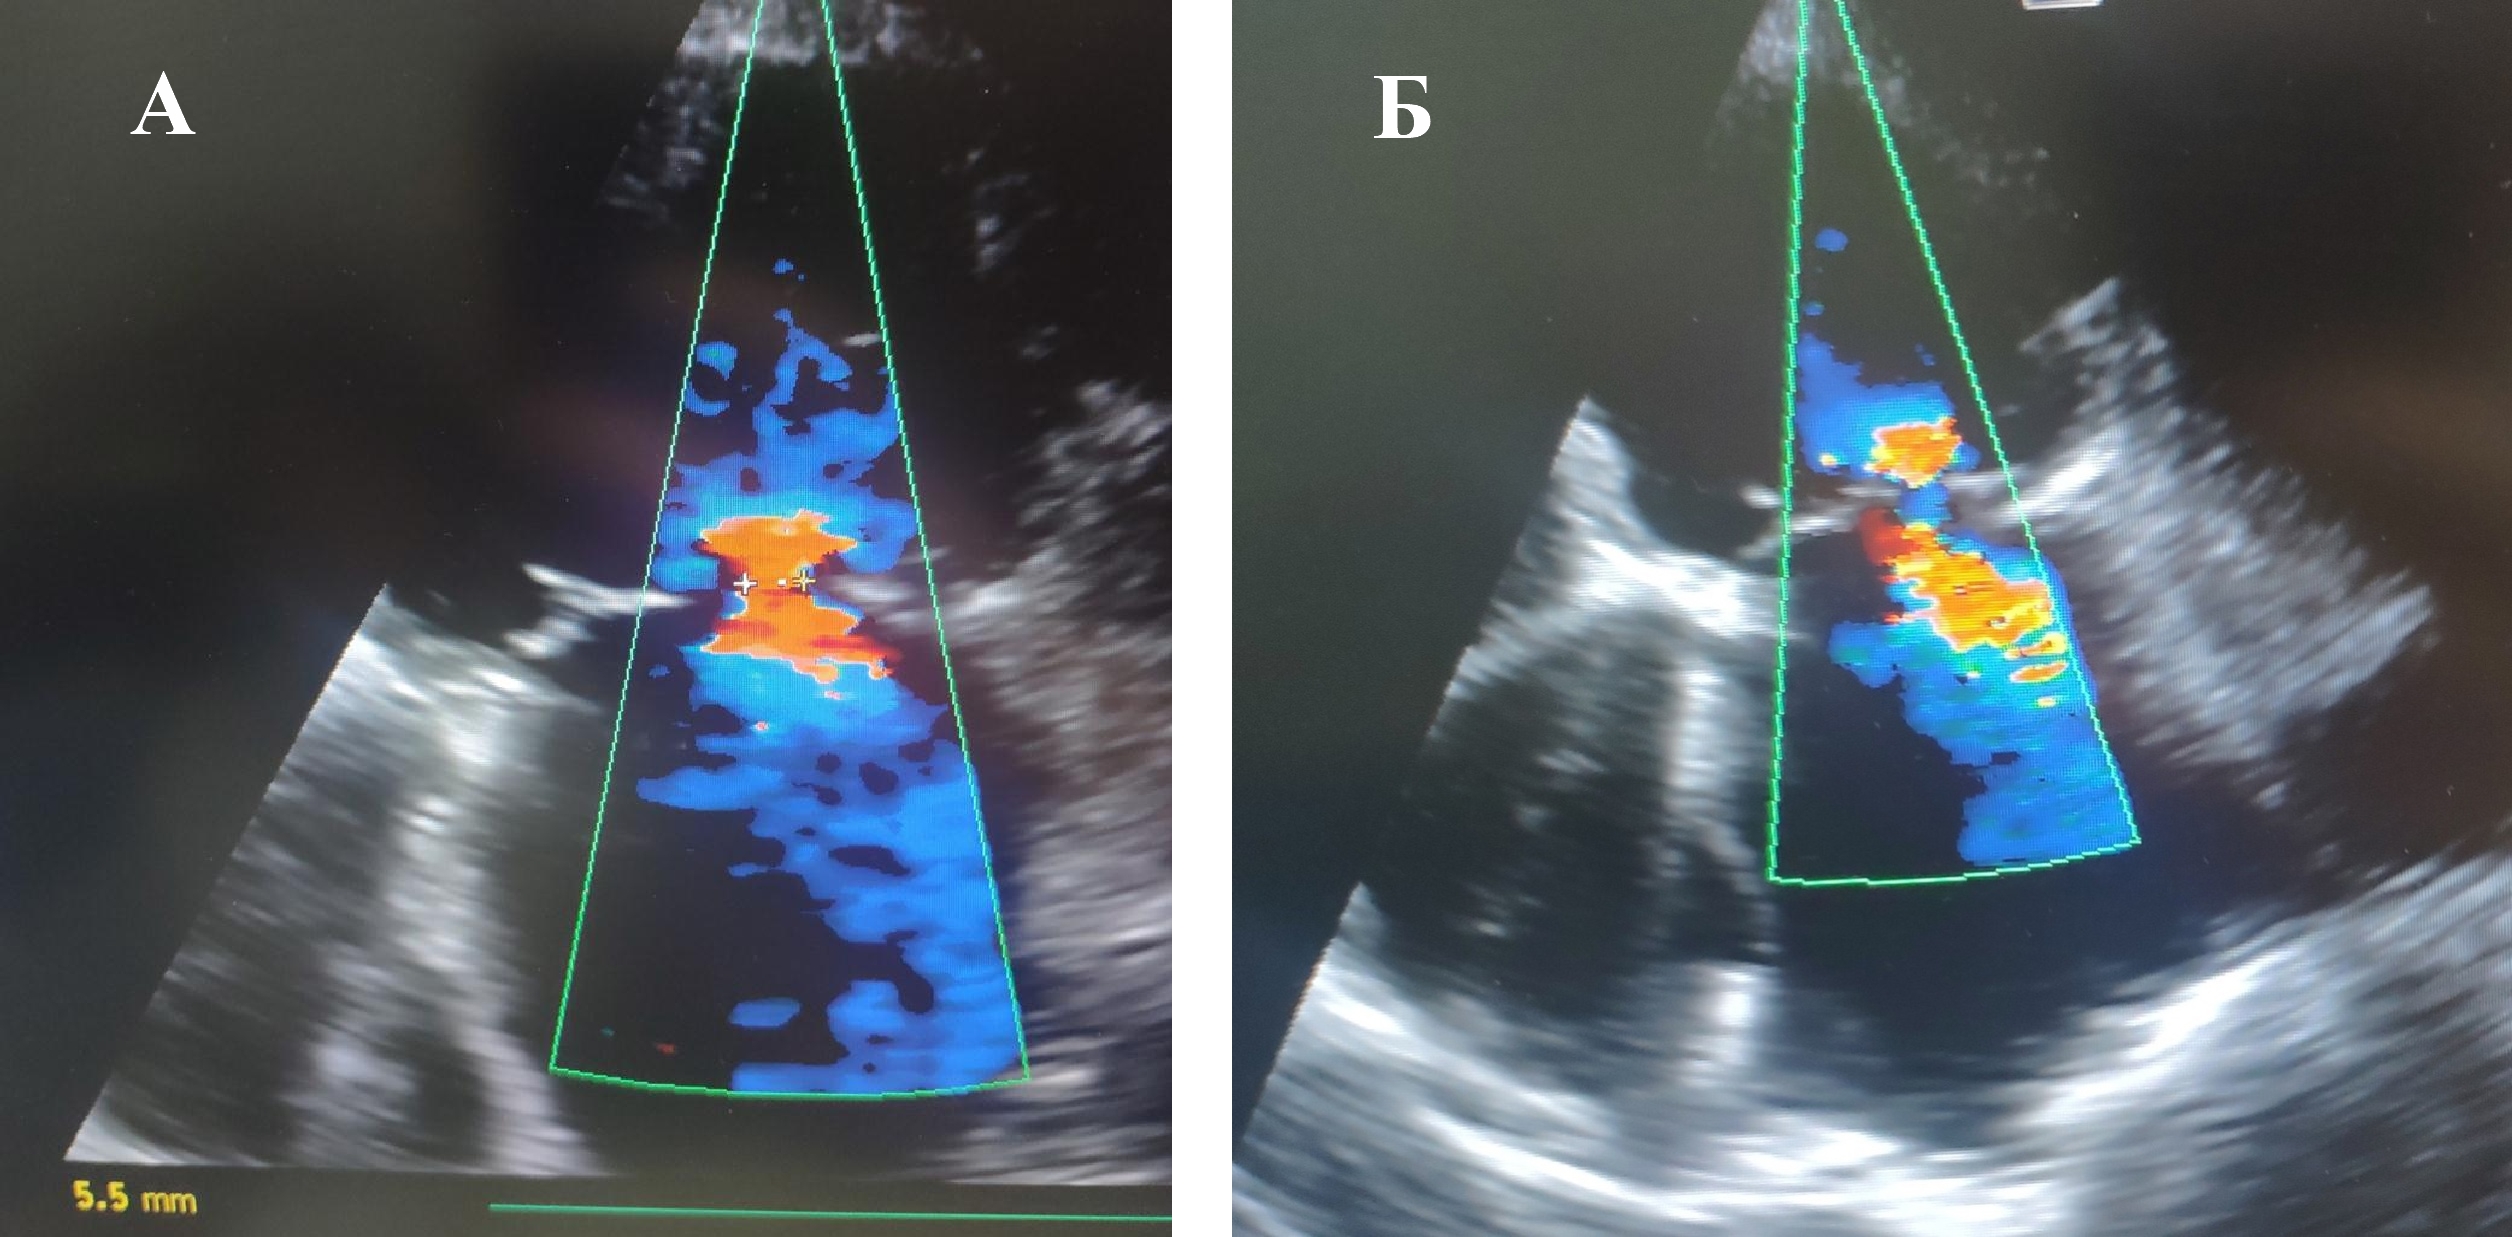

Fig. 1. Visualization of Mitral Insufficiency using color Doppler imaging before the surgical intervention: A — before insertion of Intra-Aortic Balloon Counterpulsation; B — with the working Intra-Aortic Balloon Counterpulsation in the early postoperative period.

In group 1 with the application of IABC, a statistically significant reduction in the degree of MIn (based on the change in the diameter of the v.c.) by 58% (р < 0.05) in the early postoperative period (Fig. 1B) and by 54% (р < 0.05) more than six months after the surgical intervention. This parameter remained at this level for a long observation period, with a minimum of 12 months.